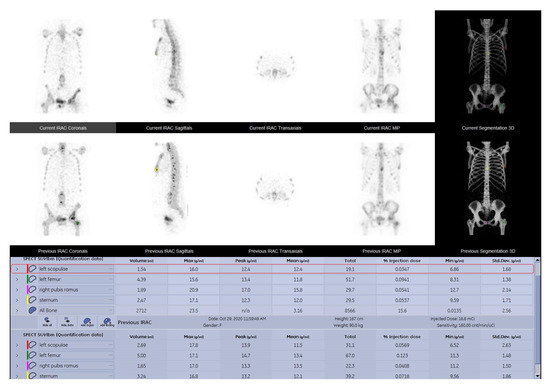

3.2. Assessed Parameters Comparison

| Mean Values of Assessed Parameters | ||||

|---|---|---|---|---|

| Tumor volume | SUVmax | SUVpeak | SUVmean | |

| Baseline | 5.14 ± 9.28 | 25.45 ± 14.04 | 19.13 ± 10.11 | 16.74 ± 7.34 |

| Follow-up | 5.91 ± 10.65 | 21.79 ± 12.07 | 16.39 ± 9.12 | 14.17 ± 6.16 |

| Statistical sig. | p < 0.05 | p < 0.05 | p < 0.05 | p < 0.05 |

3.3. Correlation between Qualitative and Quantitative Follow-Up Evaluation

| Quantitative SPECT-CT vs. Qualitative WBS | Quantitative SPECT-CT vs. Qualitative SPECT-CT | |

|---|---|---|

| Correlation Coefficient (Spearman rho) | 0.608 ** | 0.711 ** |

| Statistical significance (p value) | p < 0.001 | p < 0.001 |

3.5. Correlation of SUVmax with SUVpeak and SUVmean

| SUVmean | SUVpeak | ||

|---|---|---|---|

| SUVmax | Pearson Correlation | 0.856 | 0.966 |

| Significance | p < 0.001 | p < 0.001 | |

| N | 249 | 249 |